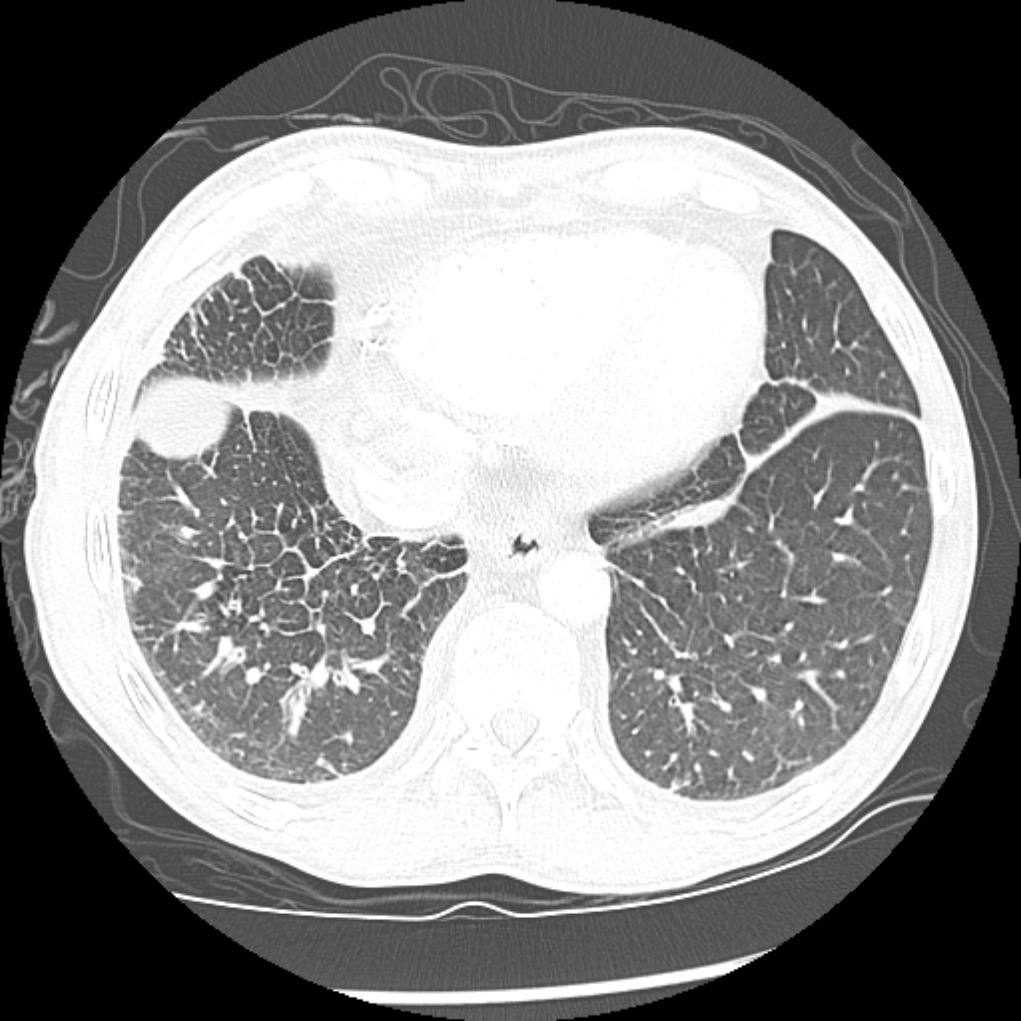

Interlobular Septal thickening (smooth)

Conditions that dilate the pulmonary veins cause smooth interlobular septal thickening. By far the most common cause of smooth interlobular septal thickening is pulmonary edema; however, the differential diagnosis for smooth interlobular septal thickening is identical to the differential for central ground glass: Pulmonary edema, pulmonary alveolar proteinosis, pulmonary hemorrhage, atypical pneumonia (especially Pneumocystis jiroveci pneumonia)

Crazy paving

Crazy paving describes interlobular septal thickening with superimposed ground glass opacification, which is though to resemble the appearance of broken pieces of stone. Although nonspecific, this pattern was first described for alveolar proteinosis, where the ground glass opacification is caused by filling of alveoli by proteinaceous material and the interlobular septal thickening is caused by lymphatics taking up the same material.